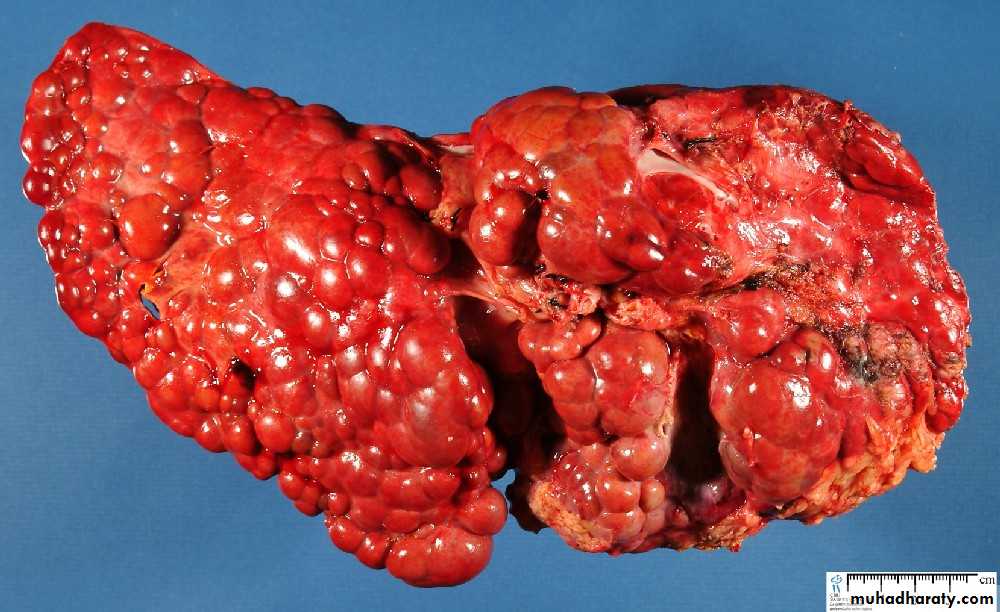

Secondary in the Liver, multiple irregular variable size nodules with central cavitations & necrosis